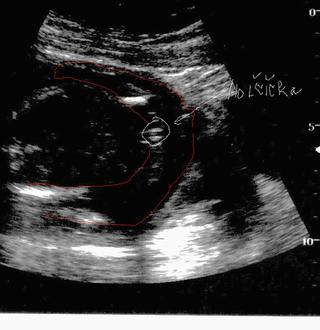

Ahojky holky jsem tu nova... Take bychom po 2 klucich chteli jeste holcicku🙂) Tak nakukuji jake rady davate 😀

@d.aniela1 Gratuluji k holcicce 🙂 Jak se zadarila? snazenickem pred Ovu?🙂 U nas u kluku to vyslo snazili jsme se Den pred Ovu o obou🙂